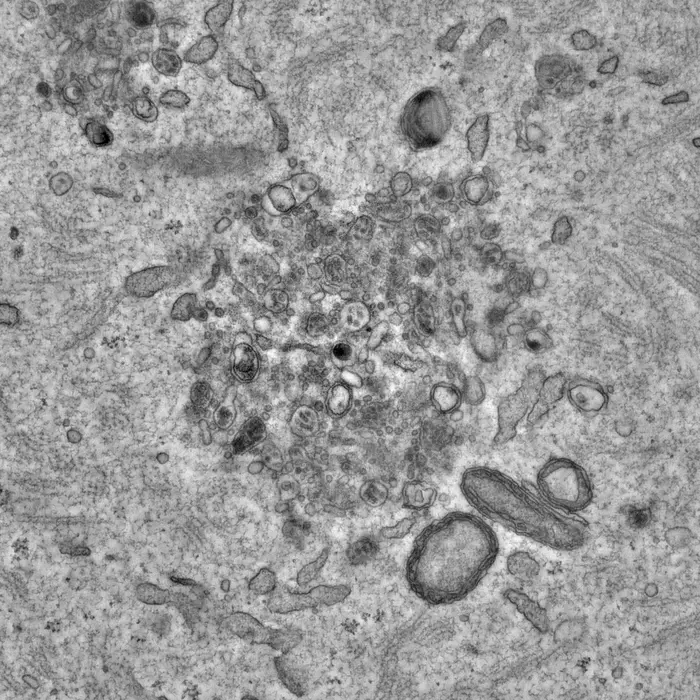

Dr. Böke’s team, led by Dr. Gabriele Zaffagnini, started by collecting thousands of immature oocytes, mature eggs, and early embryos from adult mice. Using special dyes, they observed how the protein aggregates behave in real-time using a technique called live-cell imaging. They also used electron microscopy to get a closer look and see nanoscopic details inside cells, work that took five and a half years to complete.

The researchers discovered special structures in the oocytes which they named EndoLysosomal Vesicular Assemblies – or ELVAs for short. These structures – there are about 50 per each oocyte - roam the cytoplasm, where they capture and hold onto protein aggregates, rendering them harmless. Cells have many subcellular structures known as organelles, which perform jobs much like an organ does in the body. The researchers conceptualise ELVAs as a “superorganelle” because it is a network of many different types of cellular components working together as a single unit.

The study revealed a crucial moment during the oocyte maturation stage, which is when an oocyte converts into a mature egg, preparing for ovulation and possible fertilisation. During this stage, the researchers observed ELVAs moving towards the cell's surface and breaking down the protein aggregates, essentially deep-cleaning the cytoplasm. This is the first observation of the unique strategy oocytes employ to get rid of protein aggregates.